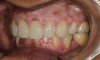

Fig 2. Preoperative frontal retracted 1:2 view.

Figure 2

A 40-year-old female patient complained of short teeth and asked for various options to improve her smile. On clinical examination, the palatal surfaces of the maxillary anterior teeth were found to be eroded, with the residual tooth structure having a smooth and shiny appearance (Figure 1 through Figure 3). In MIP, no restorative space was available, as the lower anterior teeth fit tightly into the upper palatal surfaces, making this a clinically challenging situation to treat conservatively. In most cases of conventional treatment protocols, such upper teeth are devitalized and restored with crowns that structurally leave the teeth in a compromised condition.10